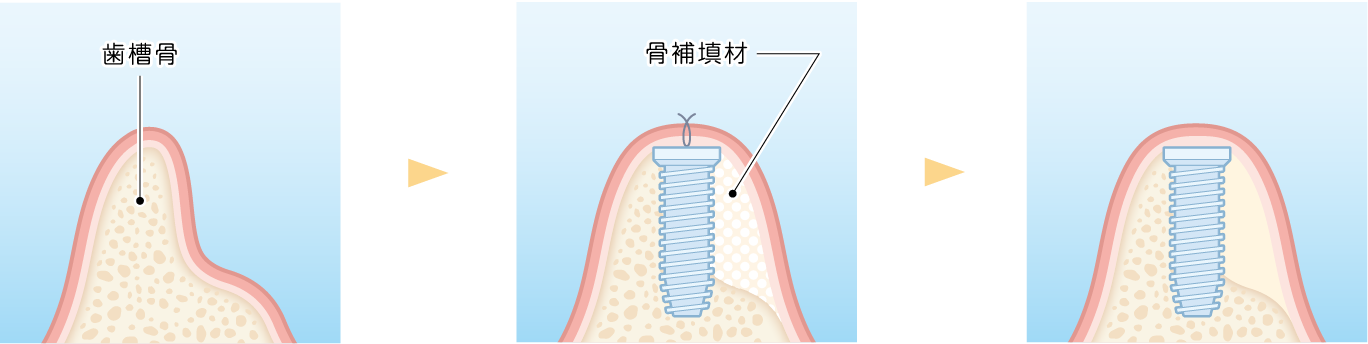

代表的な再生療法のひとつが「GBR(骨誘導再生法)」です。骨が不足した部位に自家骨や人工骨を補填し、特殊な膜(メンブレン)で覆うことで、骨の再生を促しインプラントの土台を築く方法です。

また、上顎奥歯など骨が特に薄い部位には「サイナスリフト(上顎洞底挙上術)」が適応されます。上顎洞と呼ばれる空洞の底を持ち上げ、その下に骨を造成することで、十分なインプラント埋入スペースを確保することが可能になります。